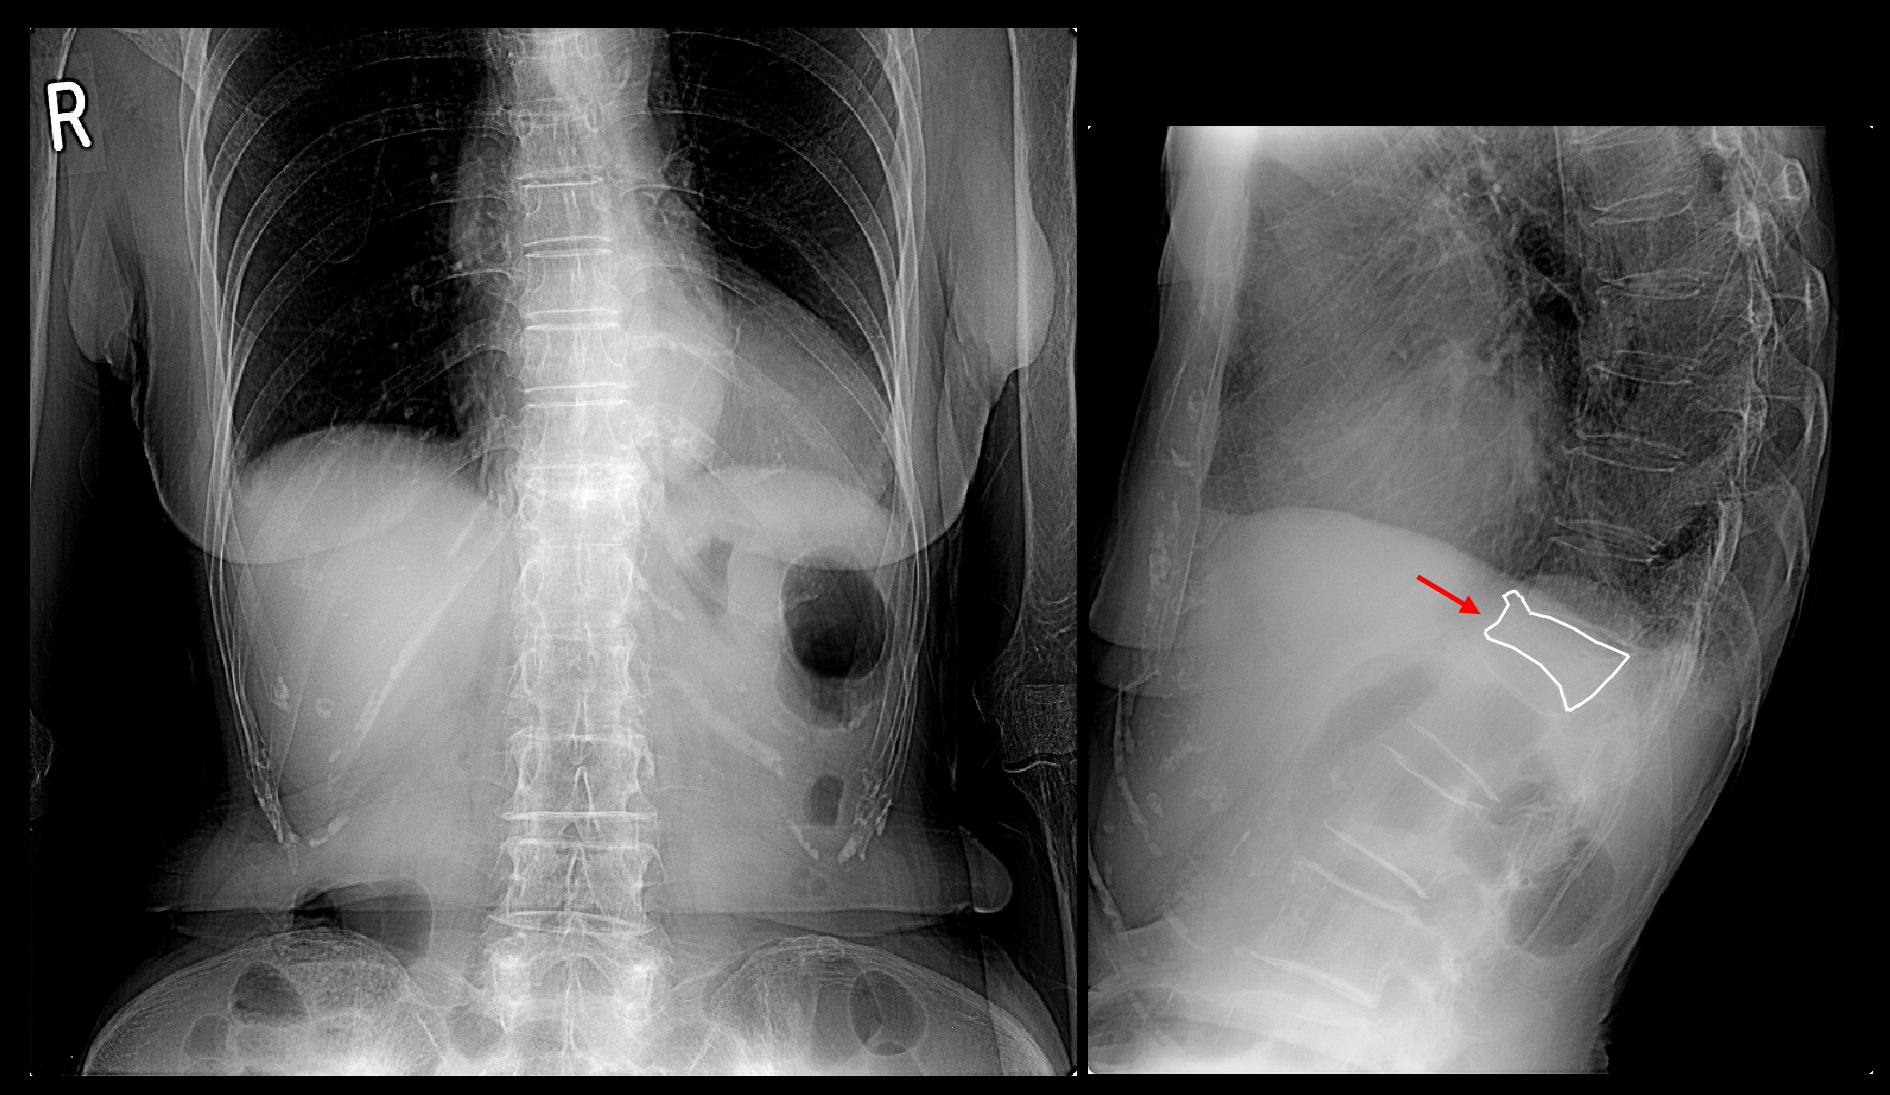

当院初診時、レントゲン像では第12胸椎(Th12)が扁平化していることが確認できました。

レントゲン像では高齢のために潰れた骨が多数みられ、どこが痛みの原因かは確認不能と判断します。